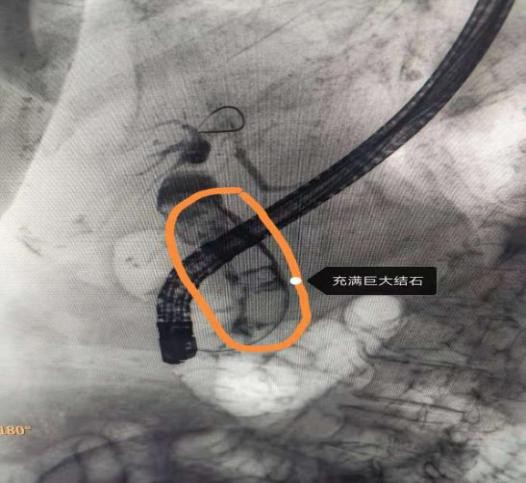

When aunt zhou was admitted to hospital, an mri examination of her galleries showed her that she was filled with huge stones, with a maximum of 2. 5 cm in diameter, with the possibility of re-obstruction, relocation and release of the shelf if she was replaced again, and repeated hospitalization for long periods of time. If the traditional “coward piping +t” is cut off, it is more traumatic for the patient and is prone to post-operative complications。

The operation, which took place on the day of the operation at the indigestion mirror centre, was conducted by prof. Slion, li and yu ki, and showed that the old cavity cavities had been cut off from the flow, that after pulling out the cavities, they chose the cavity intubation, that the fuses had entered the cavity, and that the cavities were filled with huge stones, the largest being approximately 2. 5 cm. The opening of the nipples with an extended ball cyst extends to 1. 0 cm, with no active bleeding of the nipples, followed by the insertion of a digital cholesterol, which can be seen with huge stones inside the cholesterol, followed by the insertion of laser fibers with a digital cholesterol, which are crushed one by one, and then purified with a net basket and placed into the nose. After the operation, the patient has no complications, no traumas and no stone remains in his nose。